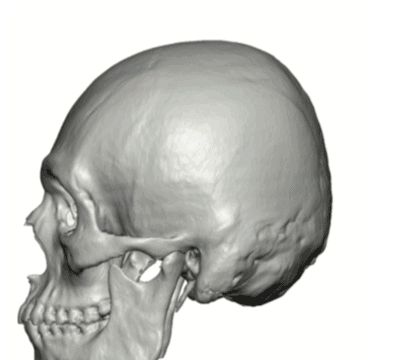

Patient 49

Desire for further skull augmentation after a primary skull implant.

Five years after an initial custom skull implant placement a new custom skull implant that increased the volume by 35% was placed.

Desire for further skull augmentation after a primary skull implant.

Five years after an initial custom skull implant placement a new custom skull implant that increased the volume by 35% was placed.